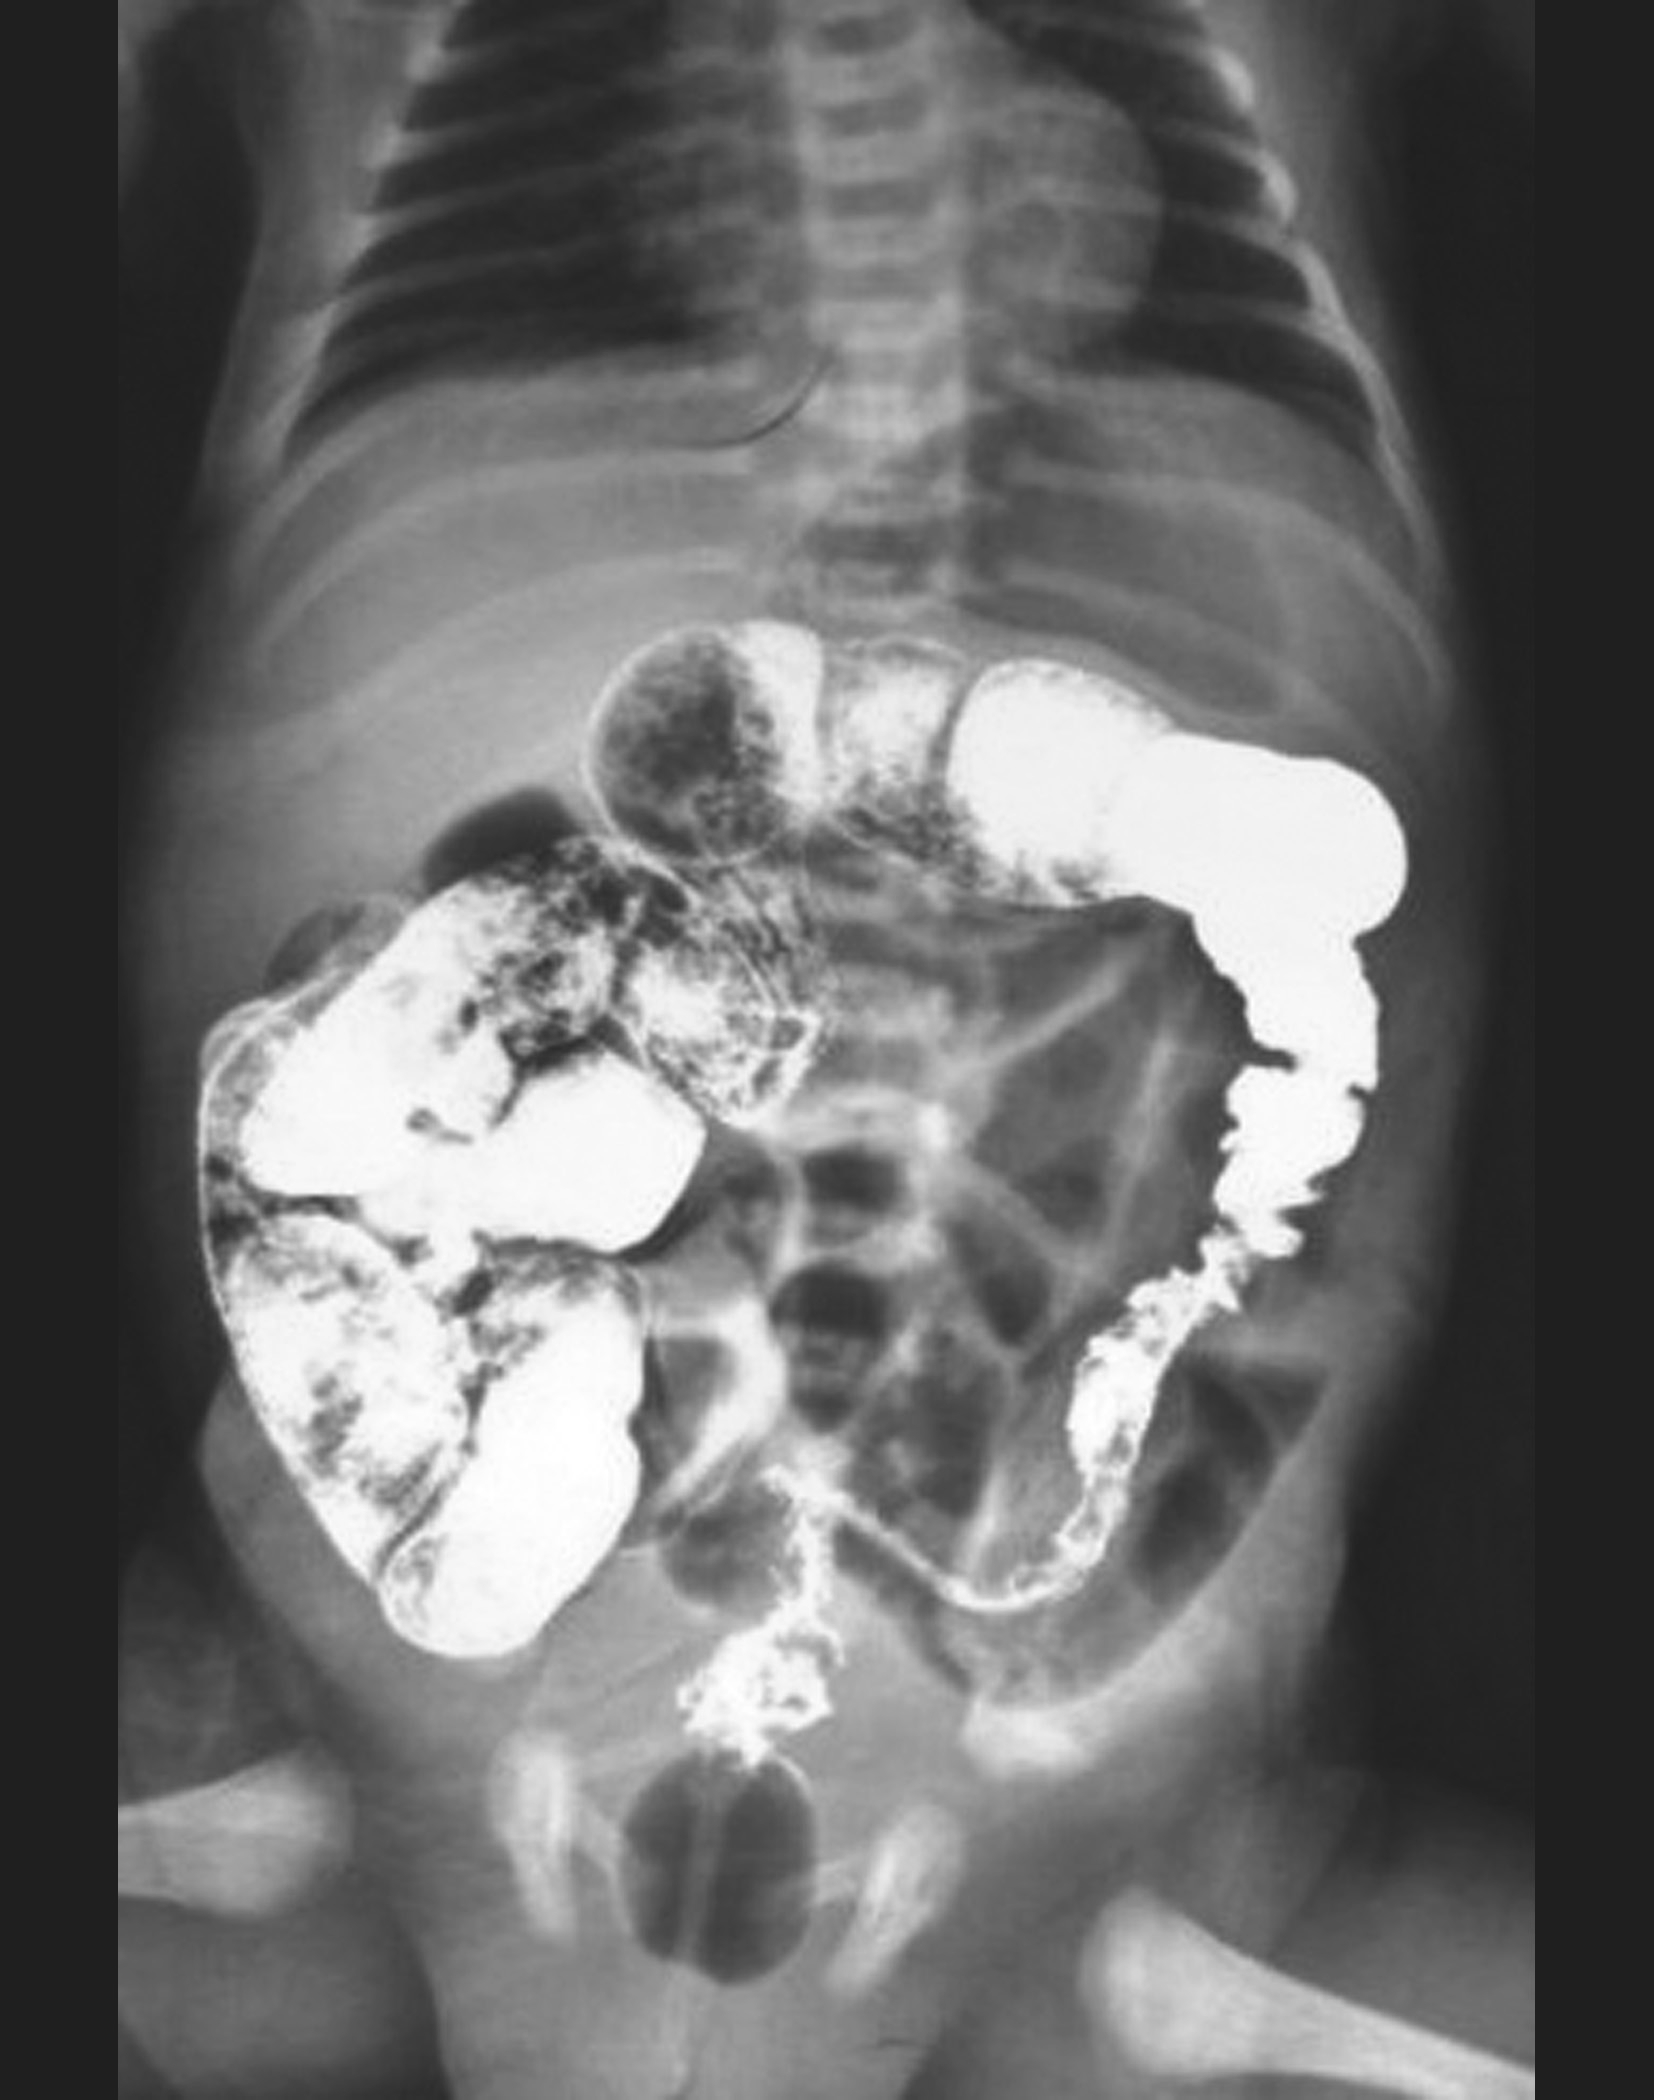

不同类型的HD钡剂灌肠检查的表现亦不同,见图3-3~图3-9。

图3-6 长段型先天性巨结肠症钡剂灌肠

狭窄段累及直肠、乙状结肠及降结肠。